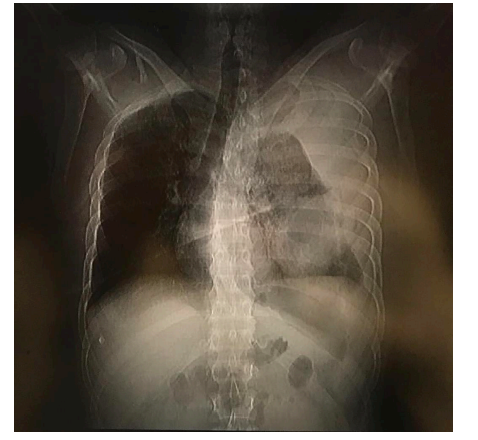

A 33-year-old immunocompetent man brought to the emergency room with symptoms of dry cough, chest pain, and dyspnea for several days and hemoptysis of five days of evolution. His clinical history revealed that he had suffered from pulmonary aspergillosis a month ago without any history of trauma and received treatment with antifungal drug voriconazole for 2 weeks; however, he had poor outpatient follow up of antifungal treatment. His vital signs on admission were as follows: blood pressure 90/50 mmHg, heart rate 114 beats/min, respiratory rate: 18 breaths/min, body temperature 36.3 °C, bodyweight: 190 lbs., height: 5’10’’, and body-mass index 27.2 kg/m2. His physical examination was remarkable for decreased breath sounds on the left hemithorax, otherwise normal examination. Chest radiograph showed a left-sided apical pneumothorax associated with pleural effusion, right mediastinal shifting, and cavitary lesion (Figure 1). Computed tomography (CT) scan of the chest confirmed the presence of a thick-walled cavitary lesion with bronchopleural fistula (Figure 2). Additionally, a complex hemorrhagic left-sided hemopneumothorax linked with the collapse of left lung was detected (Figure 3).

The patient had previously suffered from pulmonary aspergillosis, which was treated with the antifungal drug voriconazole; however, he had an inappropriate follow-up for treatment with antifungals. His radiographic images revealed a late manifestation of pulmonary aspergillosis complications. Aspergillosis is caused by a ubiquitous fungus Aspergillus spp. The fungus can be inhaled in the form of air-borne spores, and they colonize in the airways. Typically, pulmonary aspergillosis is found in individuals suffering from underlying airway diseases, such as asthma or cystic fibrosis or other lung diseases, or in immune compromised individual [11,12]. Zhang and colleagues (2010) reported a patient with a 20-year history of asthmatic disease suffering from recurrent pneumothorax and pleural aspergillosis [12]. In contrast, our patient had no history of underlying pulmonary disease, yet he developed aspergillosis, which could be due to his impaired immune system. Moreover, when aspergillosis is not treated properly, the colonies of Aspergillus spp. remain in the pleural cavity, which primarily leads to the formation of bronchopleural fistula, followed by pleural cavity infection resulting in the cavitary lesion [13]. Likewise, the cavitary lesions and bronchopleural fistula in our patient represented unsuccessfully treated aspergillosis. One of the devastating complications of pulmonary aspergillosis is massive hemoptysis [11] as seen in our patient. No causal relationship between spontaneous pneumothorax and aspergillosis has been elucidated till date. Hence, it is less likely that spontaneous hemopneumothorax in our patient is correlated to previous Aspergillus spp. infection.